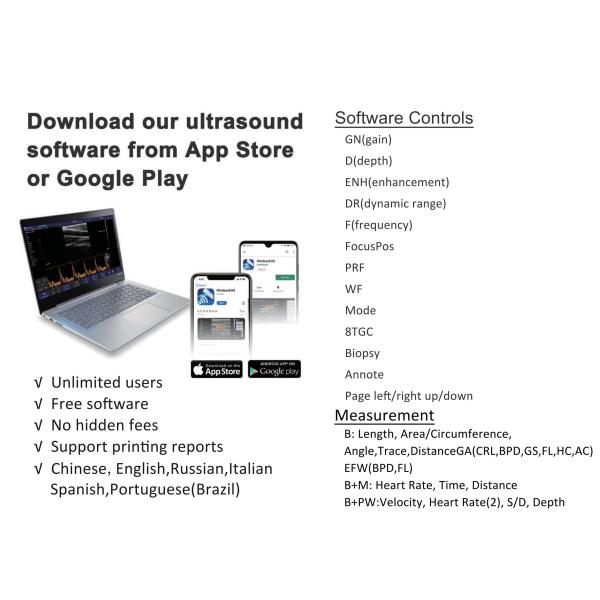

Type : Doppler Ultrasound Equipment,Portable Ultrasonic Diagnostic Devices,Veterinary Ultrasound Scanner

Imaging mode : B+B,B+M,M

Name : Cardiac portable ultrasound machine price,Cardiac Portable Color Doppler Ultrasound,Cheap Ultrasound Machine,Wireless Color doppler Ultrasound Probe

Product name : Full Digital Color Doppler Diagnostic System,medical ultrasound,Transvaginal ultrasound scanner,Cheap B/W ultrasound machine with trolley

Item : Color Doppler System,ultrasound baby scan machine,Doppler portable ultrasound machine

Display mode : B,B+B,M,B+M

GEN4proCT is Wireless Wifi dolppers Convex Array Probe Type Ultrasound Scanner. This wireless Wifi Convex Array Probe with integrated ultrasound circuit boards inside,then realize the functions of a ultrasound scanner(ecografos). It can be uesed at many occasions such as In emergency clinical, hospital ward inspection. In addition, CT is easy to poerate because it has unique design with three buttons which is an ecografo portail or portable ultrasound machine.

G10cx G10ct Portable Ultrasound Scan Machine Transducer Wireless Doppler Ultrasound Probe Images |